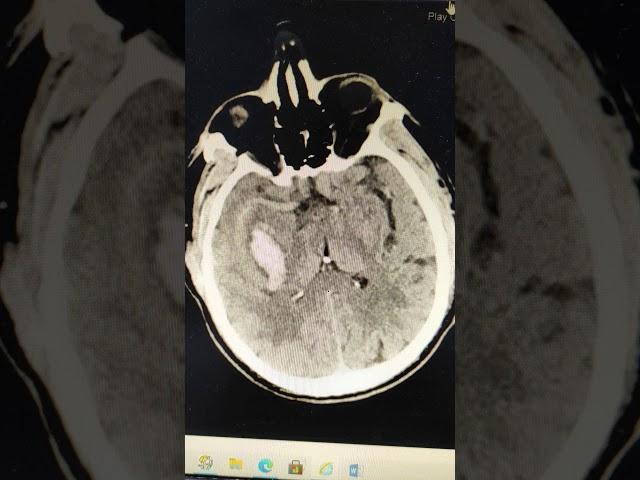

Hemorrhagic Stroke during hypertensive crisis 60yo M

Hemorrhagic Stroke during hypertensive crisis 60yo M